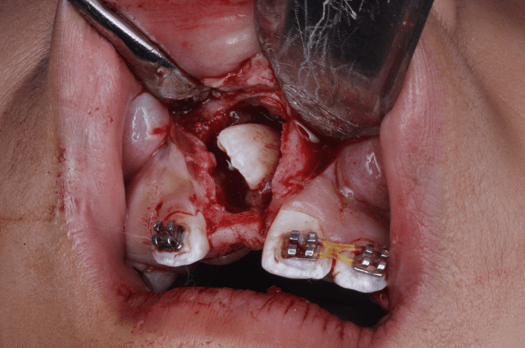

Dentro del procedimiento quirúrgico se colocó anestesia infiltrativa supraperióstica en la región vestibular y palatina del diente 1.1, se realizó incisión combinando abordaje de frenectomia labial y supracrestal con diseño romboidal con descargas en región de dientes 21 y 12, exposición de diente 11 incluido mediante osteotomía con fresa 702 para posterior colocación de botón para traccion (Fig. 12 y 13). Se programó cita de control en 8 días y retiro de puntos en 15 días desde el día de la intervención quirúrgica.

Fig 12. Ventana Quirúrgica y frenectomía labial

Fig 13. Fotografía colocación de botón cóncavo con cadeneta para tracción